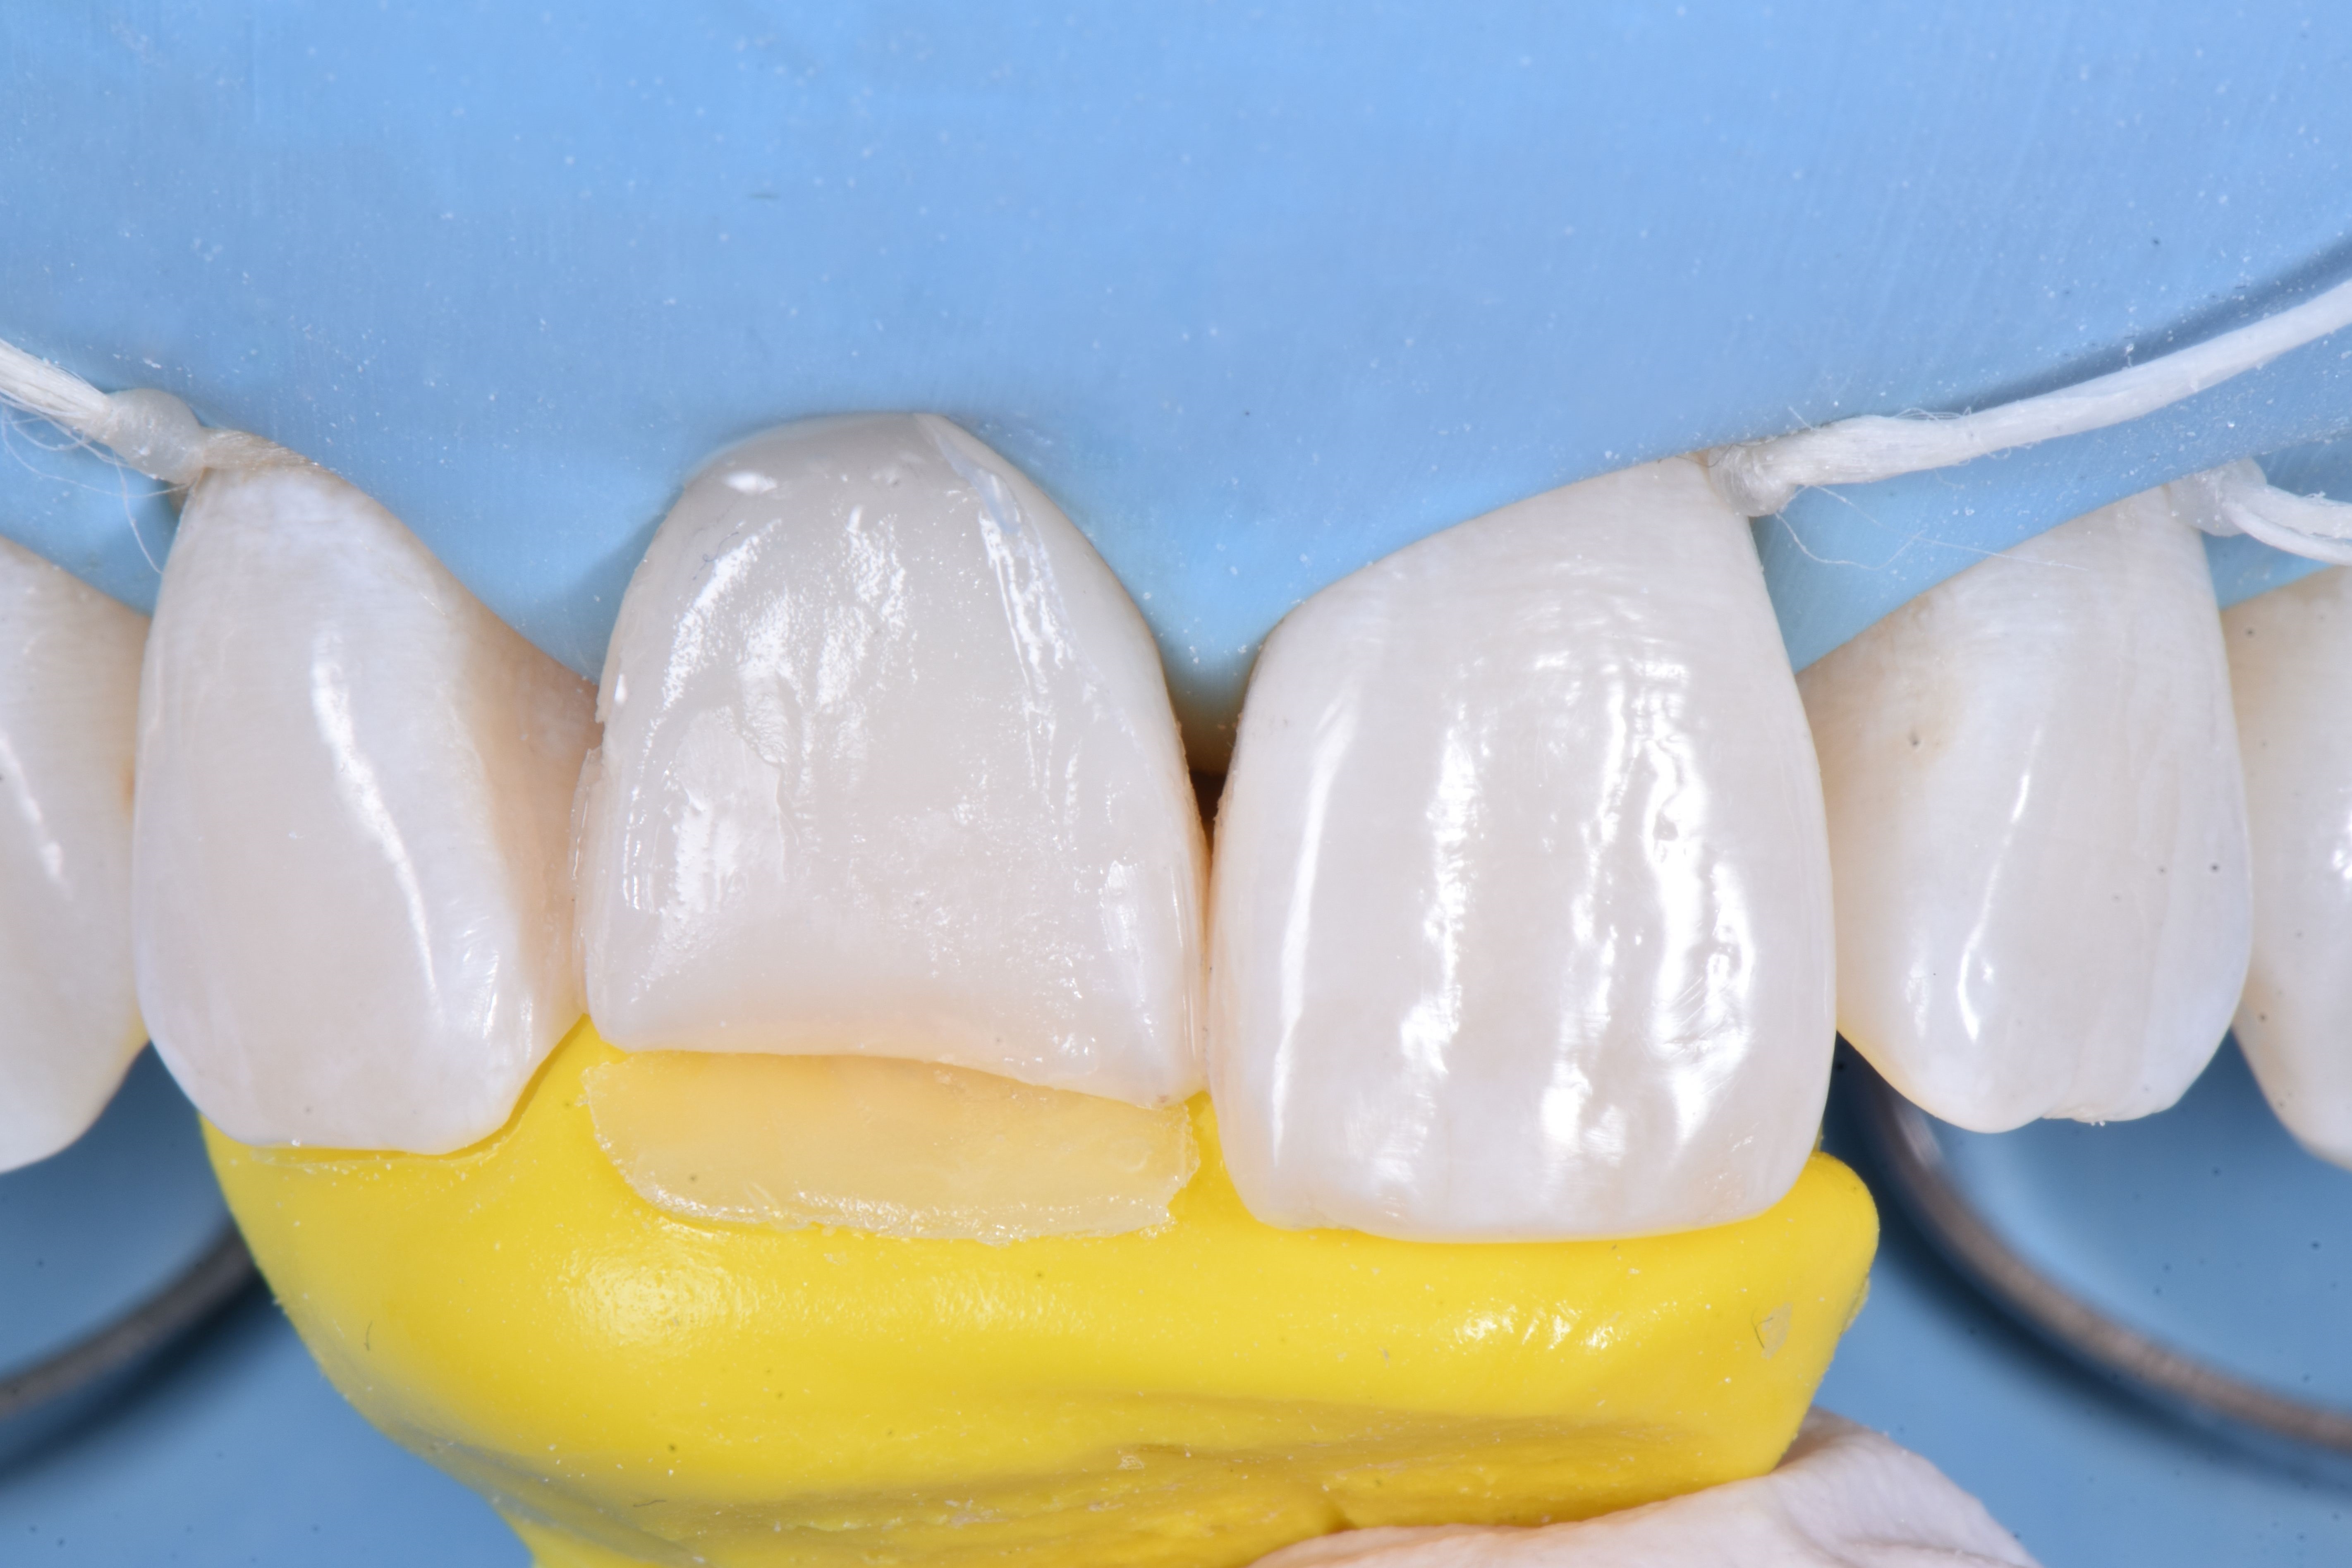

W dniu zabiegu, po wykonaniu miejscowego znieczulenia, ząb 11 odizolowano za pomocą koferdamu, rozszerzając izolację na pierwsze zęby przedtrzonowe (ryc. 4).

Następnie usunięto pękniętą rekonstrukcję kompozytową i wykonano niewielkie zukośnienie, a całą powierzchnię zęba 11 wypiaskowano tlenkiem glinu w proszku 27 μm (ryc. 5).